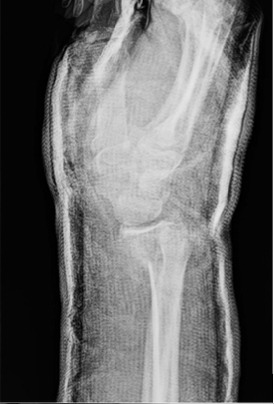

Patient one: A 14-year-old, right-hand dominant female presented to the emergency department (ED) with pain in her right wrist following a fall while roller-skating. No numbness or weakness was noted on the physical exam, and peripheral perfusion was normal. The patient had full extension and retropulsion of the right thumb. Imaging was obtained in the ED, demonstrating a non-displaced, Salter-Harris II distal radius fracture and avulsion of the right ulnar styloid process. No reduction was required. The patient was treated with a reverse sugar tong splint and discharged. The following day, she presented for an outpatient follow-up. Repeat imaging in the splint was obtained, demonstrating a Salter-Harris II distal radius buckle fracture [Figure 1]. The splint was removed and replaced with a short arm cast.